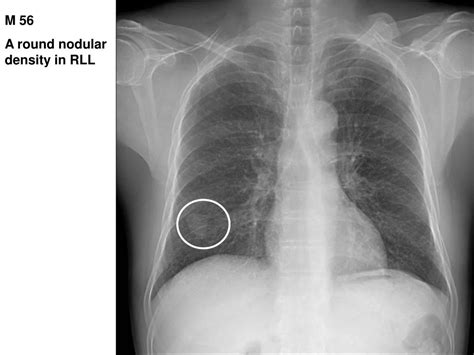

Discover what a node in lung CT scan findings means. Learn about pulmonary nodules, the difference between benign and malignant growths, and why follow-up imaging is essential for lung health. Understand diagnostic procedures, risk factors, and when to consult a specialist for a comprehensive lung nodule assessment to ensure early detection and peace of mind.